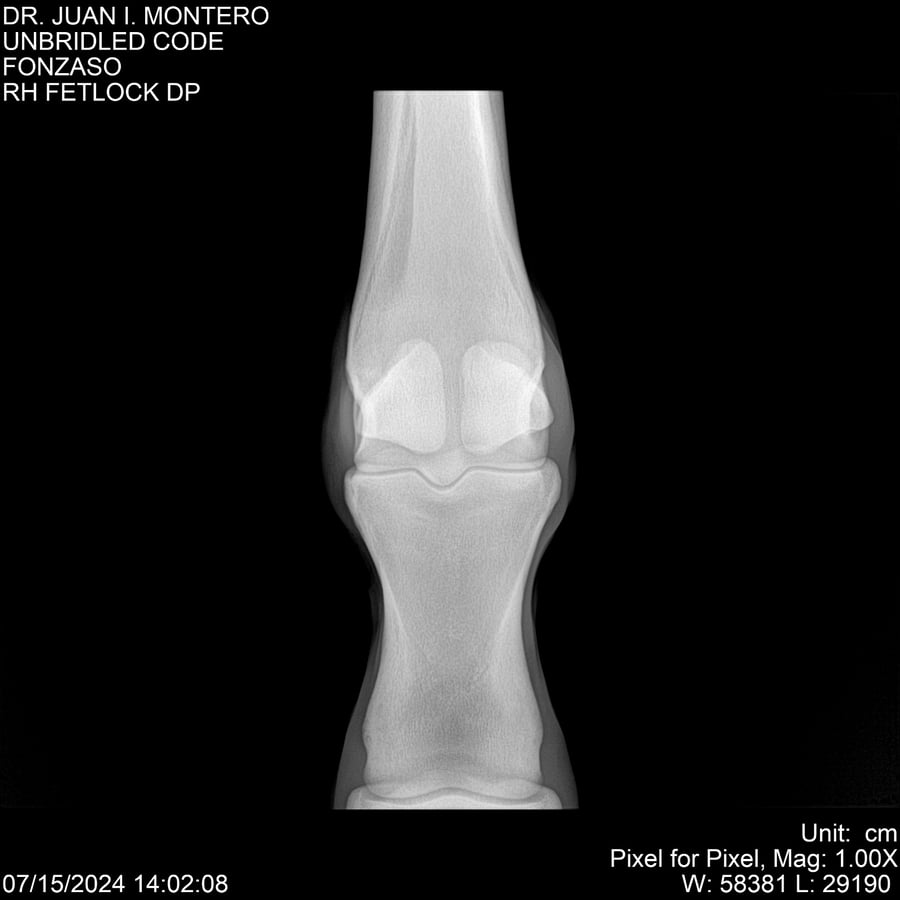

• Empresa: Abelenda N. R., Walter Hugo